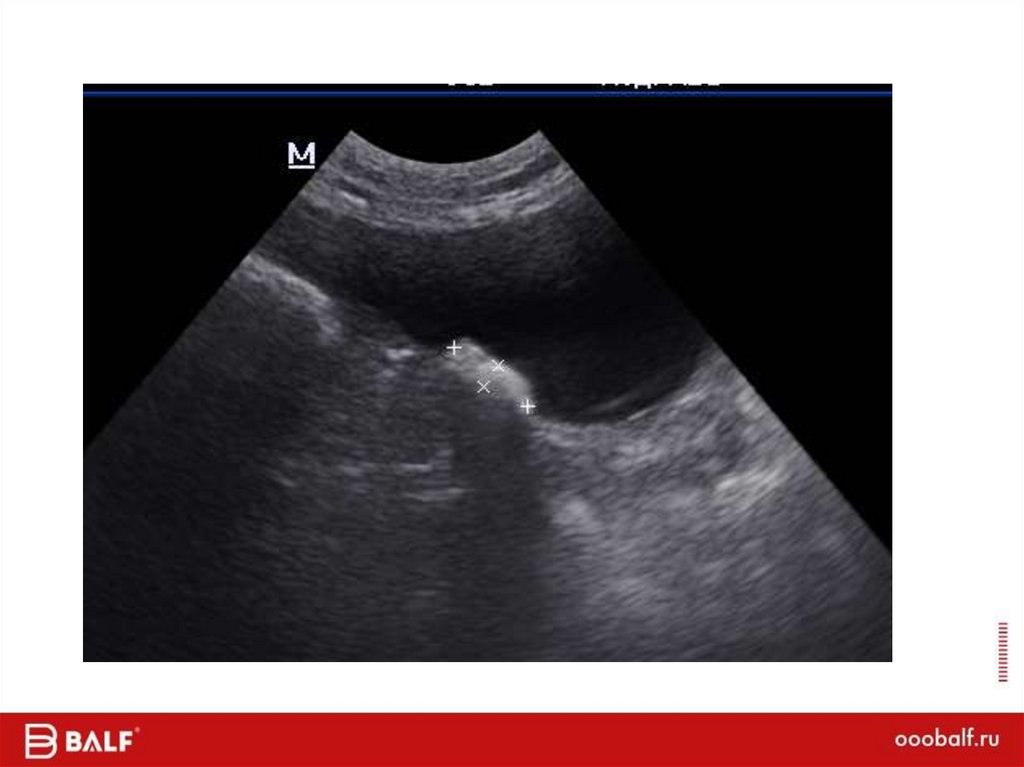

23.89M

41.